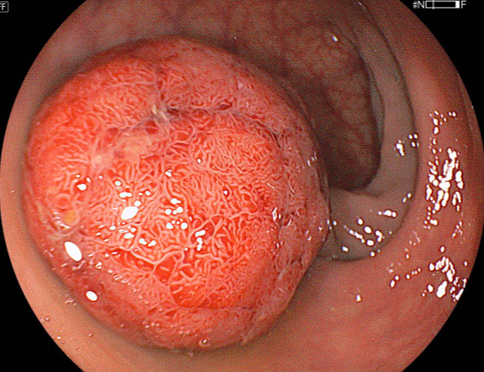

S状結腸の30mmの大型隆起性病変

LCIモードにおける弱拡大観察画像